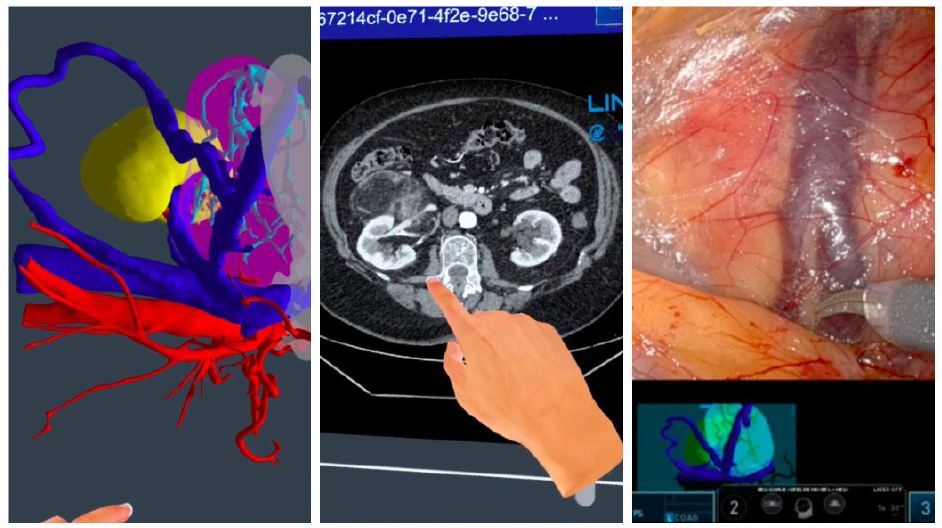

The lesion on patient C was of a slightly smaller size, so we decided to underwent a robotic partial nephrectomy. The aforementioned procedure was made feasible thanks to the assistance of a three-dimensional model, which was employed during surgical procedure. This model was created beforehand on the basis of the imaging tests performed. The neovascularization present in the lesion was optimally identified and controlled (Figure 6). No complications were observed during surgical procedure and the patient was discharged on the third postoperative day.

Figure 6: Correlation between preoperative 3D reconstruction and CT scan with intraoperative findings.